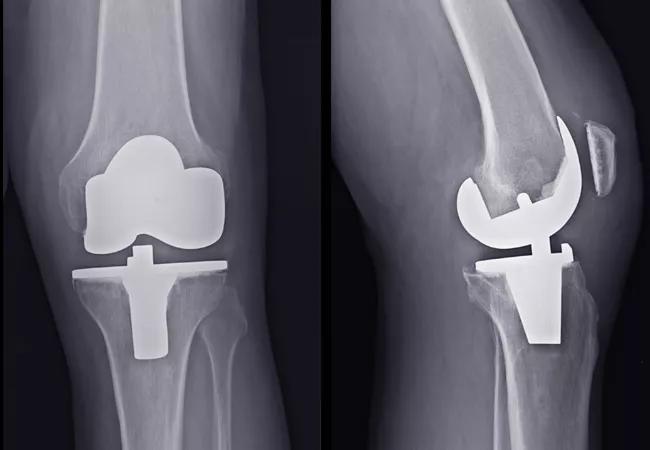

The Impact of Neuromuscular Quadriceps Stimulation on Total Knee Replacement Outcomes

To address this lack of data, Cleveland Clinic’s Orthopaedic & Rheumatologic Institute has designed a study to assess applying NMES to the quadriceps in the preoperative and postoperative phases of a total knee replacement care algorithm. Our hypothesis is that using NMES both pre- and postoperatively can improve functional outcomes following total knee replacement (TKR).

The current standard for rehabilitation after TKR consists of guided exercise therapy for up to 12 weeks. This includes inpatient, home and outpatient therapy. The surgery and rehabilitation are highly successful at reducing or eliminating pain experienced preoperatively. However, quadriceps femoris muscle (QFM) strength, overall function, and knee range of motion are often worse than preoperative levels for as long as six months after surgery and in some cases for many years. Such quadriceps muscle strength impairments after TKR have been largely attributed to voluntary activation deficits and can lead to diminished functional performance such as decreased gait speed, decreased balance that can lead to falls, and decreased stair-climbing and chair-rise abilities.